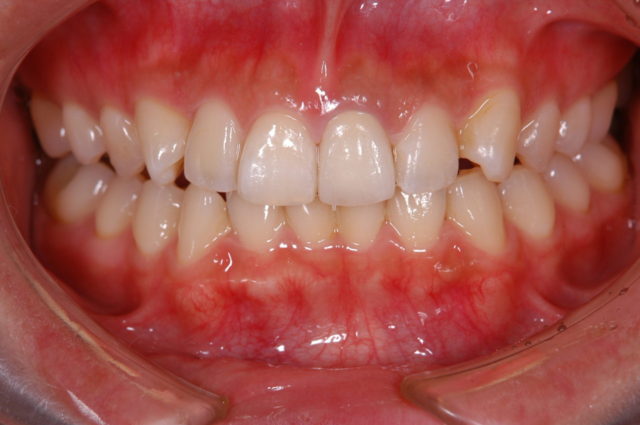

after

| 年代/性別 | 40歳 男性 |

| 主訴 | 右2番揺れる、左右1番やり替えたい |

| 治療方法 | 右2番インプラント及び、左右1番オールセラミッククラウンによる審美治療 |

| 治療期間 | 11ヵ月 |

| 費用 | 825,000円(税込) |